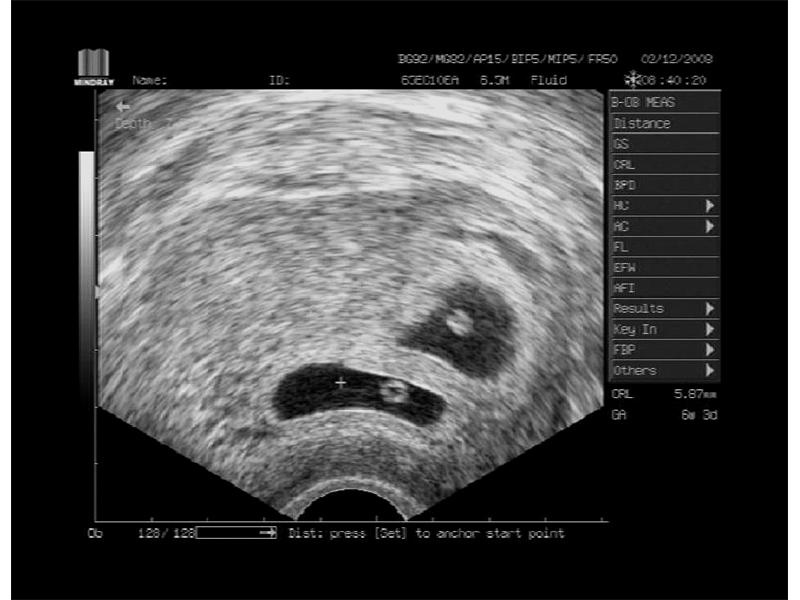

jsou to dvojčátka